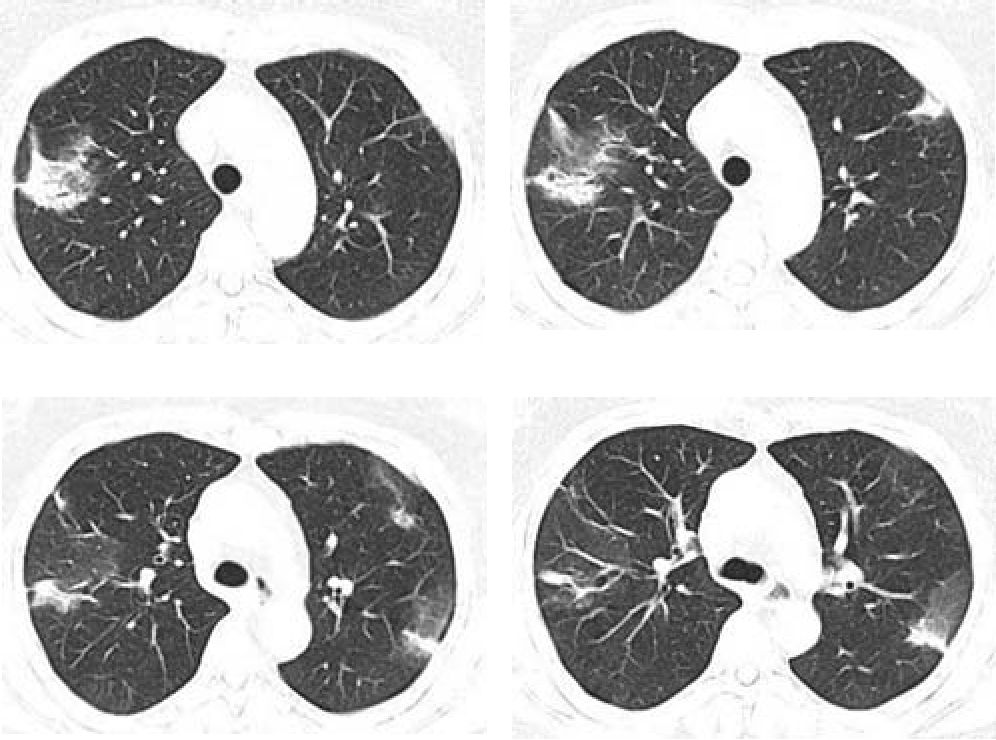

- Одновременно с зонами консолидации присутствуют «лоскутные» участки «матового» стекла (рис. 8) - важный симптом, описанный впервые G.R. Epler, имеющий место у 80% пациентов [3].

Рис. 8. Компьютерная томография органов грудной клетки при КОП. Аксиальная проекция.

а, б - субплеврапьно расположенные участки неоднородного уплотнения легочной ткани с четкими границами, с тракционно расширенными бронхами.

в-г - участки консолидации легочной ткани чередуются с участками уплотнения легочной ткани по типу "матового стекла".

По статистике на КТ в 90% случаев определяются субплевральные и перибронхиальные уплотнения легочной ткани, чаще в нижних долях легких. У 60% больных имеются участки «матового стекла». Уменьшение степени выраженности "матового стекла" при динамическом наблюдении свидетельствует об эффективности проводимой терапии.